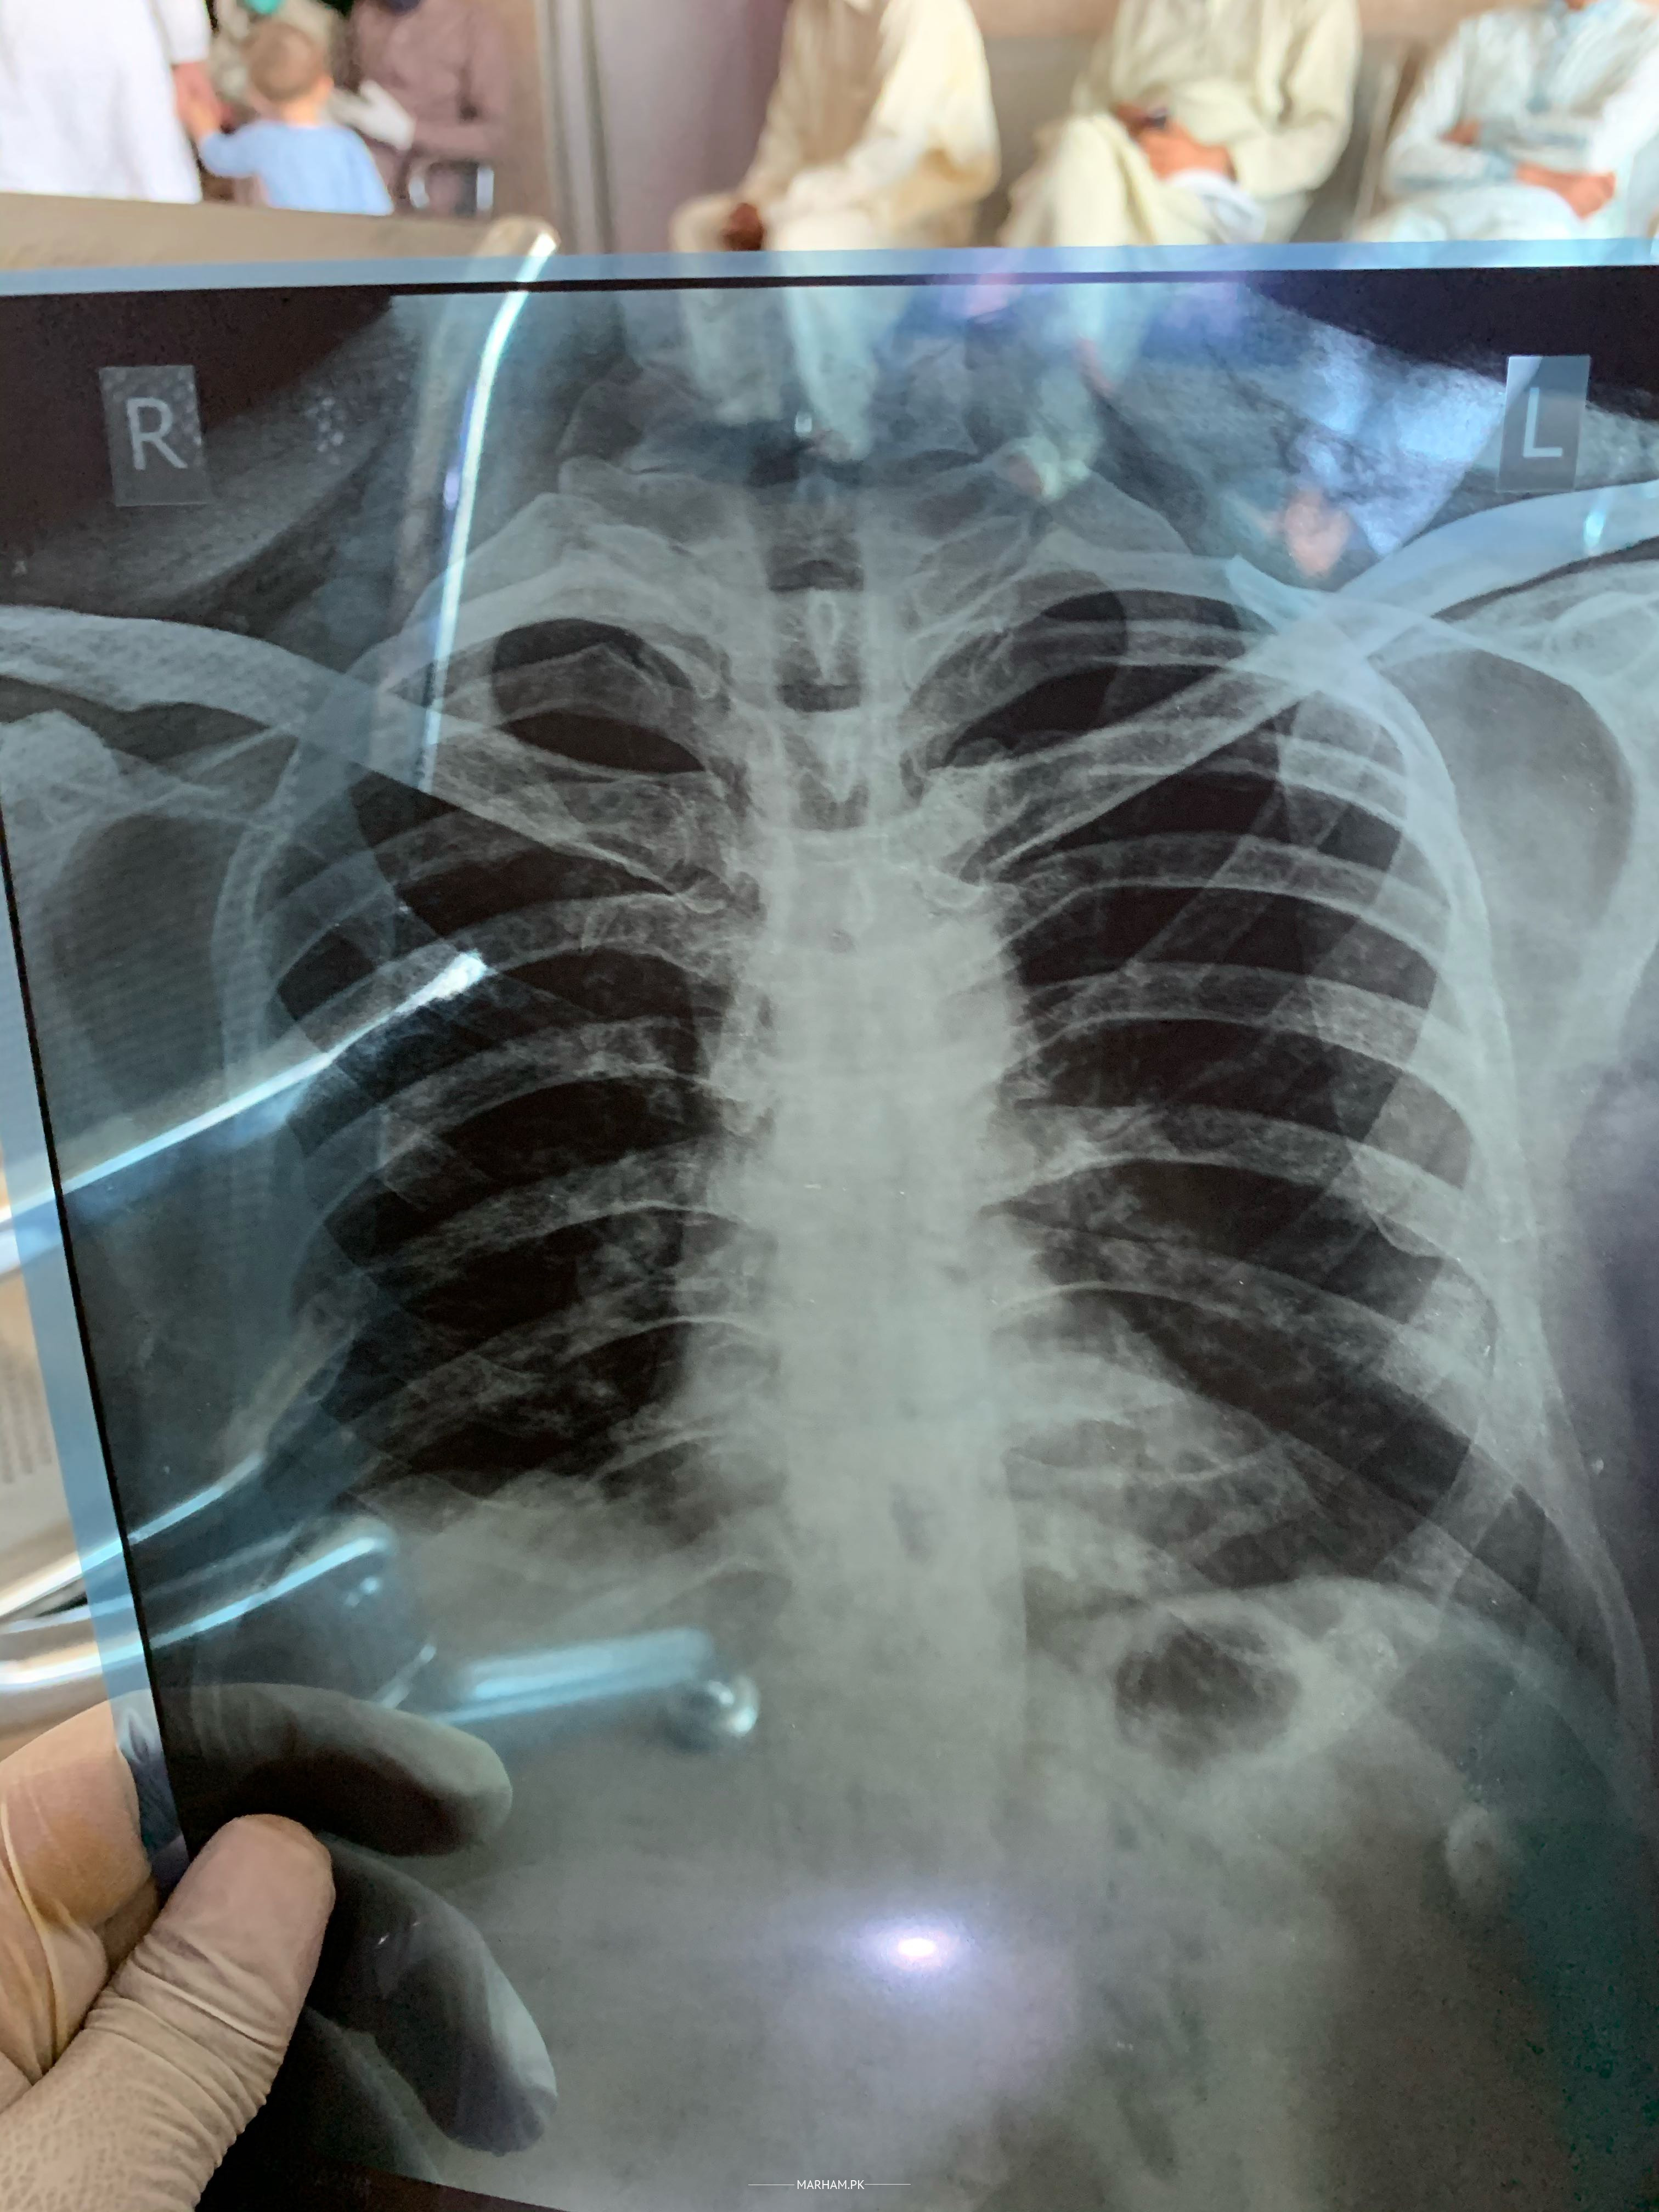

chest xray seems to be fine.

And cough and breathing issues can be due to multiple reasons.

Need to evaluate it further.

Aslam o alikum . Patient is not having pneumonia or any suspicion of covid on this xray . If patient is smoker or have history of breathing problem and have cough then you can consult with me for details of management of patient . Right now no pneumonia bt changes OF COPD are present . For which take my appointment . Will discuss in detail and he will be alright INshaa ALLAH

cardiophrenic shadows are not clear. Is he a smoker? How often does this occur? Have you gone for covid PCR?